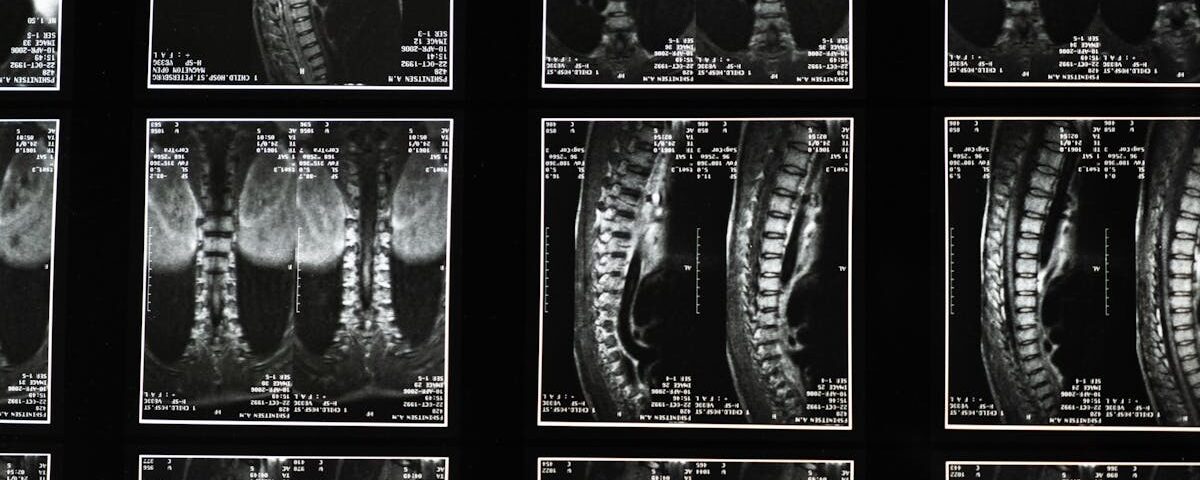

La sciatique se manifeste par des douleurs le long du nerf sciatique, qui s’étend du bas du dos jusqu’aux jambes. Elle est souvent due à la compression du nerf, causée par des problèmes tels qu’une hernie discale, une sténose spinale ou des tensions musculaires. Cette douleur peut se traduire par des sensations d’engourdissement, de picotement et parfois une faiblesse musculaire.